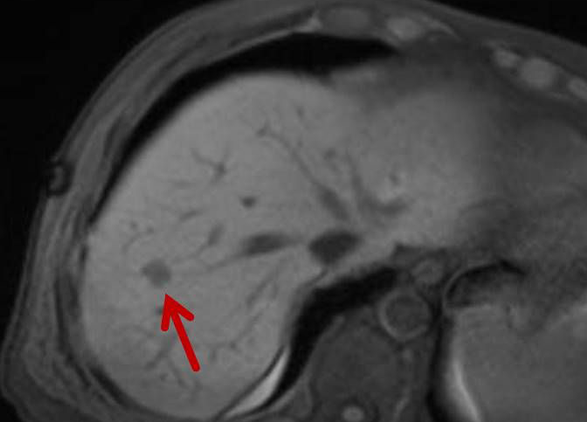

Die minimalinvasive Thermoablation ist eine Therapieoption für Leberkarzinome und Lebermetastasen. Voraussetzung hierfür ist, dass bestimmte Bedingungen wie Tumorgröße, Anzahl und Lage des Zieltumors erfüllt sein. Ob ein Lebertumor mit einem thermoablativen Verfahren (Mikrowellenablation oder Radiofrequenzablation) sicher und effektiv behandelt werden kann, wird vor der Therapie interdisziplinär mit Kollegen aller für diese Fragestellung relevanter Fachrichtungen besprochen.

Bei der perkutanen Thermoablation von Nierentumoren werden spezielle Applikatoren unter CT- oder MRT Bildgebung in den Zieltumor eingebracht. Durch Hitze wird der Tumor zerstört.